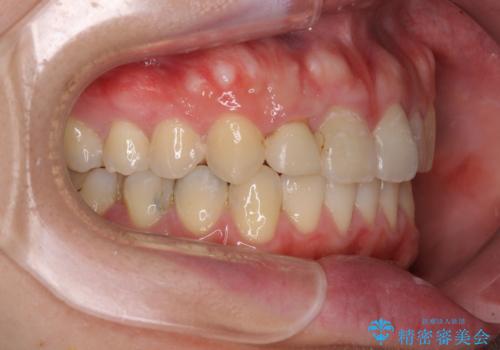

- 上下のデコボコと奥歯の咬みにくさを気にして来院された患者様です。

上顎骨の幅が下顎骨よりも小さいので、拡大装置により骨幅を広げて上下関係を改善し、その後インビザラインにて歯並びを整えることとしました。

上下の骨幅を改善したことで、スムーズに歯列矯正を行うことができました。

奥歯の咬み合わせを改善する必要があったため、治療は長期化しましたが、きっちりと仕上げることができました。